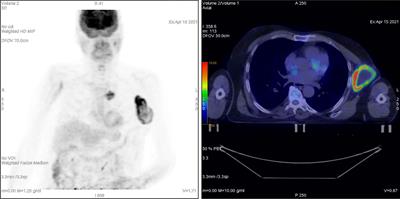

Is Performance of Fluorine-18-fluorodeoxyglucose Positron Emission Tomography/Computed tomography (CT) or Contrast-enhanced CT Efficient Enough to Guide the Hilar Lymph Node Staging for Patients with Esophageal Squamous Cell Carcinoma?